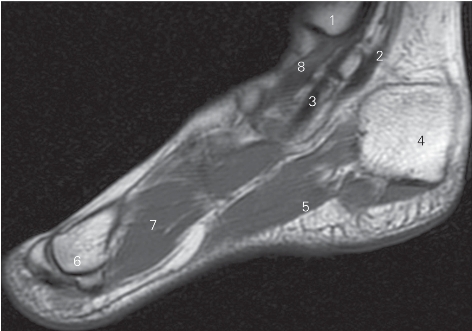

图5-59 经内踝管的足冠状断层MR T1加权图像

1 胫骨 tibia 2

长屈肌 flexor hallucis longus

3 趾长屈肌 flexor digitorum longus 4 跟骨 calcaneal

5 趾短屈肌 flexor digitorum brevis 6 第一跖骨 1st metatarsal bone

7 足底肌 sole muscle 8 胫骨后肌 tibialis posterior